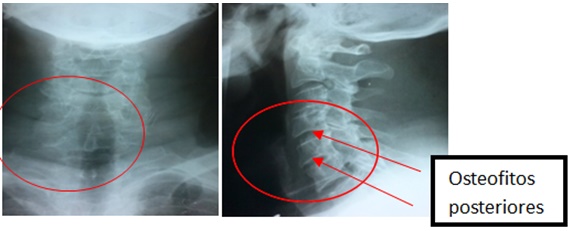

En el examen físico se buscó la presencia de dolor a la palpación de esa región anatómica y resultó negativo (imagen 2). Esta paciente permaneció muy sintomática a pesar del tratamiento, se añadía parestesias, fatiga del miembro y dolor cervical acentuado, con la misma irradiación a la región escapular y al miembro del mismo lado. El caso fue evaluado en el grupo básico de trabajo, con el diagnostico presuntivo de una cervicobraquialgia a determinar la etiología; se indicaron radiografías de columna cervical, que mostraron rectificación de la lordosis cervical, con la presencia de moderados a severos cambios degenerativos a predominio de los espacios C5, C6 y C7, con marcado estrechamiento del espacio articular, esclerosis subcondral, osteofitos posteriores (imagen 3), lo cual justificaba su sintomatología. Se concluyó clínica y radiológicamente como una radiculopatía cervical espondilótica, consecutiva a una espondilosis cervical degenerativa, se indicó tratamiento conservador medicamentoso y fisioterapéutico intensivo, incluyendo la medicina tradicional, con evolución satisfactoria a mediano plazo.

IMAGEN 3. Rx en dos vistas columna cervical